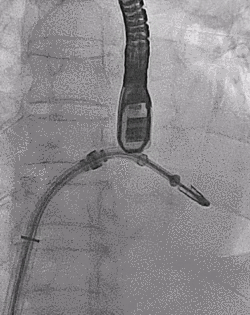

王焱、王斌教授团队通过术前和台北荣民总医院(Taipei Veterans General Hospital)宋思贤教授进行了详细的讨论并制定了最优的手术策略,同时术中视频连线获得宋思贤教授的技术支持,国产自拍 超声内科苏茂龙教授负责术中超声心动图引导。患者全麻以后,在经食道超声心动图和X射线引导下,经股静脉入路,将MitraClip瓣膜夹顺利送至二尖瓣前后叶交界中心处,成功捕捉二尖瓣前叶A2和后叶P2,经超声心动图反复确认瓣叶夹持牢固后,测定有效夹持长度11mm,评估反流量降至微量,释放瓣膜夹,超声心动图评估瓣膜夹位置和功能良好,测定左房压降至11/6mmHg,再次评估反流量仍为微量,手术顺利完成。

▲ MitraClip释放